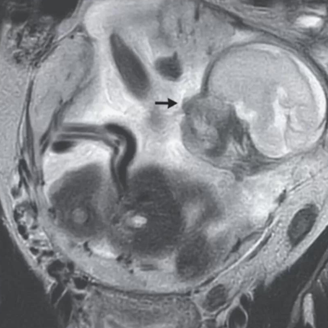

Após sentir fortes dores de cólica por 10 dias, uma mulher foi até o hospital procurar ajuda e teve que ser internada depois de descobrir uma gestação de 23 semanas. A gravidez era ectópica (fora do útero) e o feto estava se desenvolvendo em um saco gestacional fora do útero, entre o estômago e o seu intestino.

O caso raro foi compartilhado em um artigo do New England Journal of Medicine no último sábado (9). Segundo relato médico, a mulher se queixava de dores abdominais e inchaço na barriga.

Foto: New England Journal of Medicine